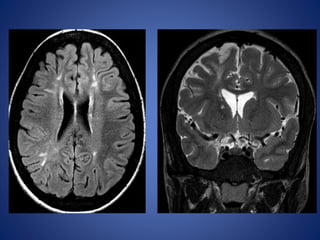

15 months old, Fever since 5 days, Right focal seizures, Right hemiparesis, Persistent

irritability.

The classic featuresthat indicate CSVT include the • “Dense triangle” or the “Cord sign,” which describe the increased density over the thrombosed venous sinus in a plain CT, • “Empty triangle” or “Empty delta (δ) ” sign in a contrast- enhanced CT. DWI is a sensitive technique for detecting areas of infarction. Parenchymal changes can be seen within minutes of injury, which allows for early identification and intervention

15 months old,Fever since 5 days, Right focal seizures, Right hemiparesis, Persistent irritability.